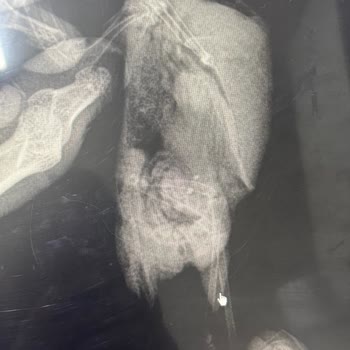

22 Nisan 2026 tarihinde Aksaray Ereğlikapı Mahallesi’indeki Tarım İl/İlçe Müdürlüğü’ne yaklaşık 5,5 aylık kedime çip taktırmak için gittim. İşlem sırasında görevliler kuduz aşısını da yapmamız gerektiğini söyleyince güvenerek kabul ettik ve kedimize Raksharab isimli kuduz aşısı uygulandı. Aşı uygula...